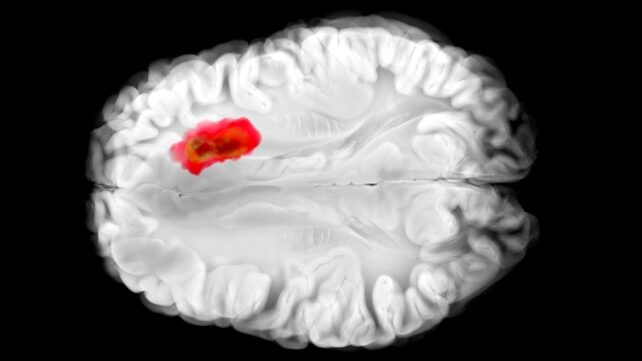

Хидралазин се користи за лекување на висок крвен притисок со децении, иако никогаш не било сосема јасно како точно делува. Ново истражување дава одговори на некои клучни прашања за овој лек – и го поврзува со една од најсмртоносните форми на мозочен тумор. Научниците од Универзитетот во Пенсилванија детално ги проучиле ефектите од хидралазин врз човечки клетки и клетки на глувци. Тие откриле дека тој го блокира специфичниот ензим наречен 2-аминоетантиол диоксигеназа (ADO), кој се смета дека има голема улога во агресивниот глиобластом (мозочен карцином). Оваа нова перспектива за хидралазин може да отвори нови патишта во третманите против ракот, а и да ја подобри неговата ефикасност во постоечките лекувања.

Истражувачите го опишуваат ADO како „алармен ѕвонец“ кој го алармира телото кога нивото на кислород паѓа, активирајќи синџирна реакција што ги стега крвните садови преку уништување на така наречениот RGS-протеин (регулатор на G-протеин сигнализација). Претходни студии покажаа дека кај глиобластом туморите, ензимот ADO е често присутен во високи количини, при што ракот го искористува да произведе хипотаурин – хемикалија што им помага на канцерогените клетки да се шират, да преживуваат подолго и да поднесат стрес. Но, со ова истражување, првпат е откриен инхибитор на ADO. Хидралазин ефективно го „замолчува“ ензимот ADO: RGS-протеините не се напаѓаат, крвните садови не се стегаат и крвниот притисок опаѓа. Во експериментите со човечки клетки од глиобластом, хидралазин всушност го запрел развојот на туморот преку блокирање на ADO. Истражувачите додаваат дека ефектот на хидралазин секако допрва треба да се тестира на луѓе со глиобластом во клинички испитувања, но наодите се ветувачки.